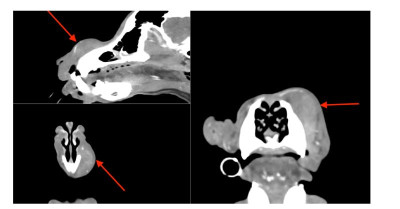

Niestety nie mamy dobrych wiadomosci od Maxa.

Dzisiaj napisała do mnie Pani Dorota:

Dzień dobry,

Przepraszam za brak wcześniejszej odpowiedzi, ale ten rok jest niestety dla nas pełen zawirowań.

Generalnie z Maksiem wszystko było super, żadnych problemów, dużo spacerów po lesie i nowy poziom integracji z naszym najmłodszym członkiem rodziny - 3letnim synkiem Jasiem - wcześniej Maks podchodził do niego z dystansem, ale w tym roku zaczęli się nawet razem bawić, a spacery z tą dwójką w ty samym czasie są teraz w końcu możliwe, co nas bardzo cieszy i daje wszystkim dużo radości. W dodatku budują nam pod domem park, więc mamy teraz nowe ścieżki na spacery.

Niestety nasz spokój zakłócił ostatnio pyszczek Maksia - bo pojawiło się na nim jakaś opuchlizna, ale przy dotykaniu jest twarde. Nie ma żadnych innych objawów, a miejsce to nie sprawia mu bólu. Aktualnie jesteśmy już po wizytach u specjalistów - i tutaj sprawa wygląda dosyć źle i poważnie, ponieważ podejrzewany jest nowotwór - kostniakomięsak, z racji, że jest to duży pies i to jest podobno typowy rak dla tej rasy. Nie mamy jednak tego jeszcze potwierdzonego w badaniach. Są to jednak przypuszczenia weterynarza onkologa.

Czekamy w tym momencie na diagnostykę.

Na wizytach nie było możliwości zrobienia badań, bo pobranie biopsji jest niemożliwe ze względu na twardość tego miejsca, a normalne rtg jest zbyt ograniczone, żeby można było to dobrze obejrzeć.

Mamy skierowanie na tomografię głowy, szyi i klatki piersiowej - do tego biopsja zmiany rozrostowej w znieczuleniu podczas tomografii.

Jesteśmy na etapie zapisu na to badanie, czekamy jeszcze na wyniki badań krwi, które mają być dzisiaj.

Cała nasza rodzina jest załamana chorobą Maksa, oczywiście podejmujemy się leczenia, ale najgorsze jest to, że przy tej opcji, którą podejrzewają weterynarze, możliwości całkowitego wyleczenia są znikome - z racji umiejscowienia tego nowotworu tuż obok nosa- nie ma opcji chirurgicznej, a chemioterapia działa tylko na ograniczenie przerzutów.

Na pocieszenie jest to, że poza guzkiem nie ma żadnych innych objawów, Maks jest w świetnej formie i lekarze są dość zdziwieni tym, że praktycznie 10 letni pies z dużej rasy tak świetnie się trzyma i praktycznie nie starzeje, bo według nich wygląda na psa max. 8 letniego.

To nas bardzo trzyma w nadzieji!

Dlatego też chciałabym tutaj porozmawiać z kimś z Fundacji - może ktoś z rodzin adopcyjnych miał podobny przypadek? Może ktoś może polecić jakiś super lekarzy albo możemy z kimś się skonsultować jak już będziemy mieć komplet badań?

Będę bardzo wdzięczna za wsparcie albo chociaż info zwrotne, czy Fundacja może nas gdzieś pokierować.

Dziękuję za kontakt, przykro mi bardzo, że musiałam przekazać takie przykre informacje :( :( :( :(

Przesyłam jeszcze jego aktualne fotki - Maksio jest bardzo pociesznym i kochanym psem z energią szczeniaka, więc na pewno tak łatwo się nie podda, a my razem z nim!

Maxiu jest po pełnej diagnostyce.

Zmiana okazała się włókniakomięsakiem :cry:

Jak pisze Pani Dorota:

Aktualnie nie tracimy czasu i Maks przyjmuje chemię metronomiczną. Do tego rozważamy operację, którą zalecił chirurg onkolog Anna Rajska Krysa z przychodni Bemowo Wet - tam robiliśmy wszystkie badania i tam są w miarę dostępne terminy jesli chodzi o wizyty, dlatego zdecydowaliśmy się na leczenie w tym miejscu.

Nie jesteśmy jeszcze zapisani na zabieg ponieważ taka operacja to duże ryzyko dla psa w tym wieku, w dodatku umiejscowienie guza jest dość kłopotliwe, bo chirurg na pewno będzie musiał zachować margines przy wycięciu i usunąć część kości z nosa :( i szukam oczywiście jeszcze innych opcji i miałam nadzieję, że jest inny sposób, ale wygląda na to, że niestety operacja jest nieunikniona.

Prosimy o mocne trzymanie kciuków za Maxa

Obraz TK 1.jpg

Plik ściągnięto 6 raz(y) 29.5 KB

Obraz TK 2.PNG

Plik ściągnięto 7 raz(y) 344.31 KB